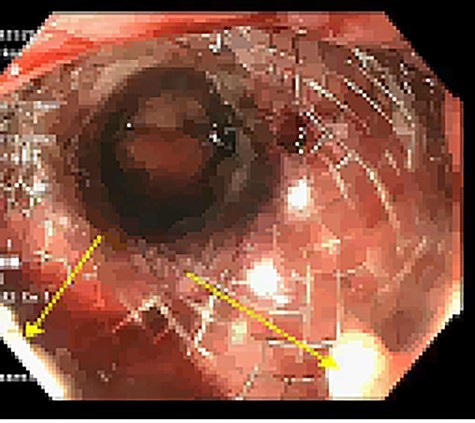

Approximately 2 months into his postoperative course, he returned with symptoms of dysphagia. esophagogastroduodenoscopy (EGD) revealed benign-appearing stenosis at the level of the esophagogastric anastomosis. This was initially dilated with a balloon. However, due to recurrent symptoms, a fully covered SEMS was placed to alleviate stricture (Figs 1, 2). The patient did well for nearly 2 months before returning with recurrent symptoms. A new web was visualized causing complete luminal obstruction (Fig. 3). This was unable to be traversed in antegrade fashion, requiring retrograde access via the jejunostomy utilizing guidewire. A pediatric colonoscope was able to be passed over the guidewire and dilate before subsequent SEMS deployment (Fig. 4). This stent was secured using 2-0 polypropylene suture via Overstitch device (Fig. 5). The initial SEMS was found to have migrated to the mid portion of the gastric conduit. However, due to the small caliber of the proximal stricture and to avoid disrupting newly deployed stent, the initial SEMS was left in place.

Retrograde guidewire, with subsequent pediatric colonoscope and SEMS placement.